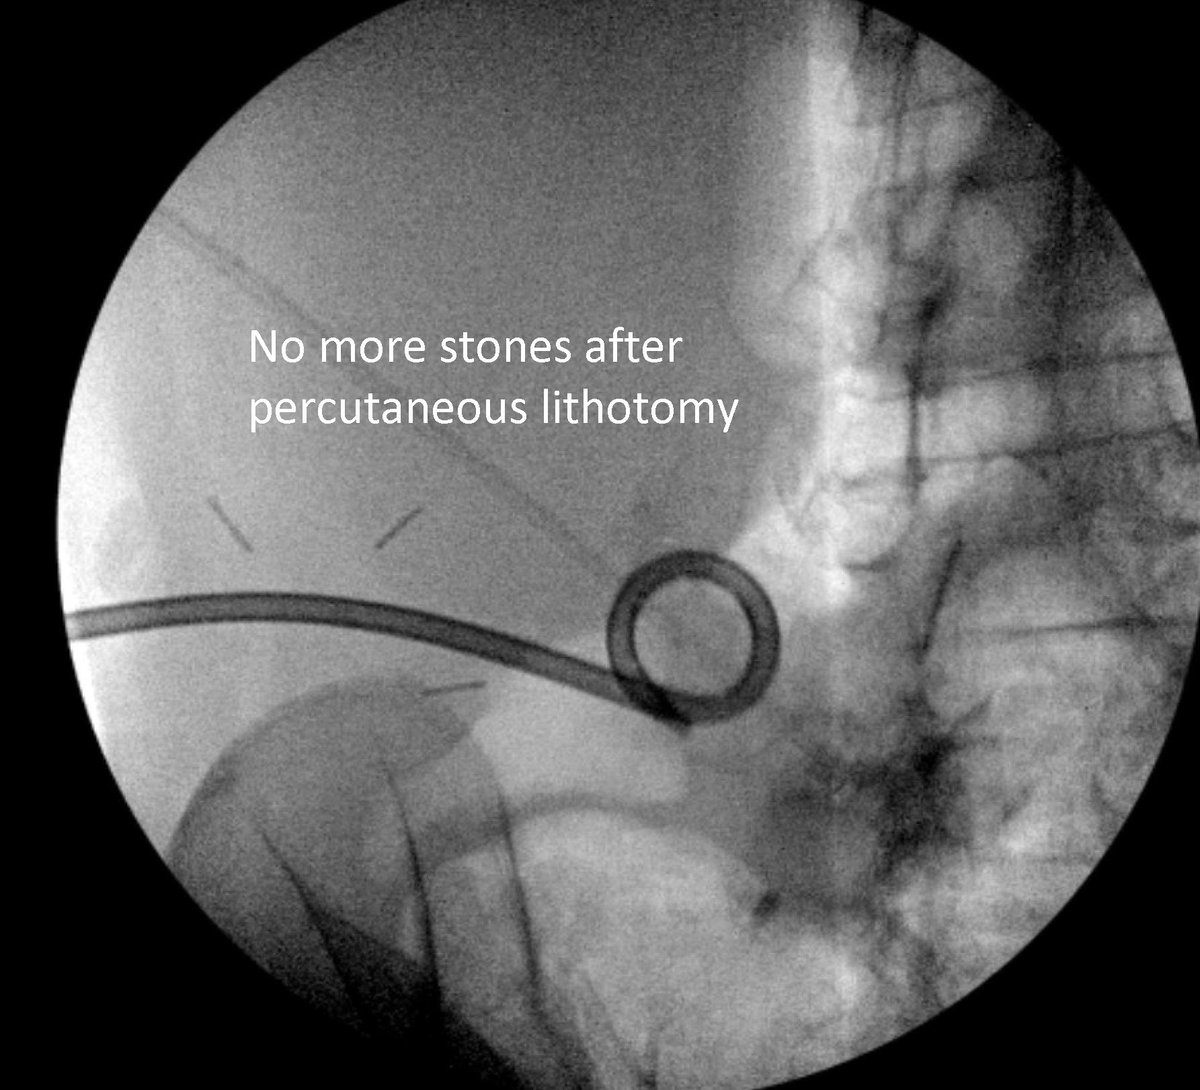

I love working with my colleagues @uabmedicine to come up with solutions for patients, like in this case. Interventional radiology (#IRad) placed a percutaneous drain into an Indiana pouch to facilitate percutaneous nephrolithotomy. The text message follow up is the best part!